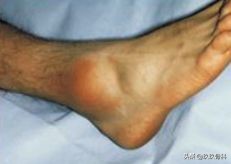

症状

- 受伤史—内翻伤,旋后伤

- 疼痛、肿胀

- 皮下淤血

- 跛行

- 活动受限

体征

- 肿胀,压痛(注意压痛最明显的部位!)

- 被动内翻后旋后时疼痛明显加重

- 注意检查踝关节有无不稳(抽屉试验、内翻应力试验、距骨侧方移动试验)